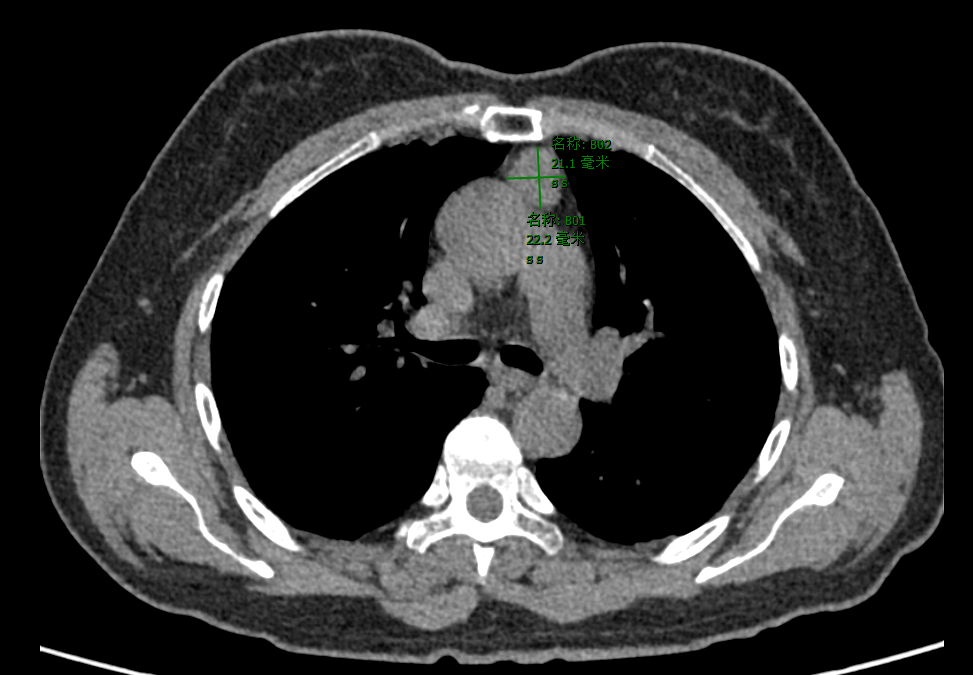

患者因胸部CT检查发现纵隔肿物,到广东医附院胸外科做进一步诊治。入院后进行了各项术前相关检查,患者心肺肝肾等功能良好,无高血压、糖尿病等基础病。纵隔肿物考虑胸腺瘤可能性大,经患者家属同意以及胸外科术前讨论后,胸外科医师团队选择达芬奇机器人辅助经剑突下入路切除纵隔肿物。

CT提示前纵隔占位